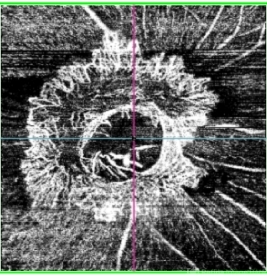

- NEOVASCULARISATION OF DISC, OCTA

Optical coherence tomography system

TOPCON DRI OCT Triton Plus swept source OCT - Description

- OCT Angiography of Optic Disc ( vitreous slab) of a 56 year old male with proliferative diabetic retinopathy showing neovascularization of disc.